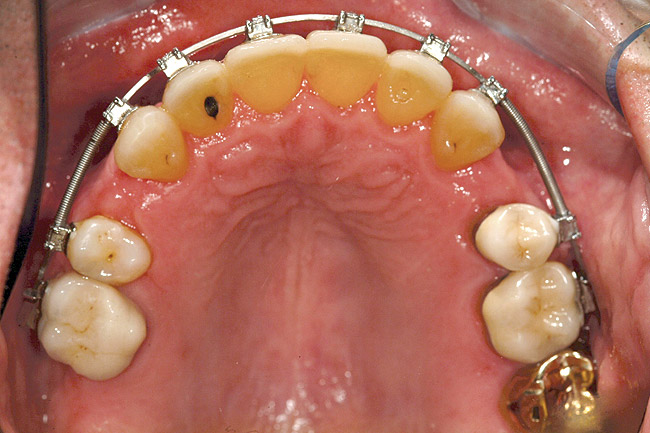

Fig 2 (and Fig 3). Corticotomy SFOT. The patient presented with unesthetic anterior bridgework that was placed at age 14 to compensate for congenitally missing Nos. 7 and 10.

Figure 2

Fig 4. Note gingival inflammation caused by biologic width violation. Provisional restorations were placed on Nos. 6, 8, 9, and 11, and corticotomies were performed from Nos. 3 to 14.

Figure 4

Fig 5. One week postsurgery with mesial buildups on Nos. 5 and 12 and thin pontics on archwire to conceal spaces during closure.

Figure 5